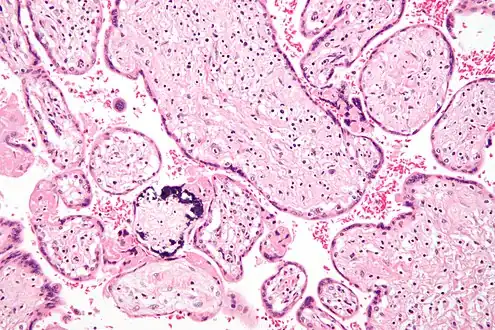

Micrograph of cytomegalovirus (CMV) infection of the placenta (CMV placentitis), a vertically transmitted infection: The characteristic large nucleus of a CMV-infected cell is seen off-centre at the bottom right of the image, H&E stain.